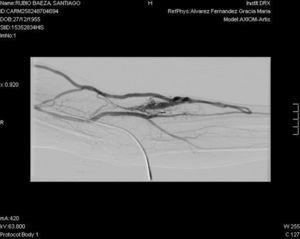

Con respecto al acceso vascular, en noviembre de 2011 se coloca catéter tunelizado de doble luz yugular izquierdo para HD. Tras seis meses comienza con edema progresivo en la extremidad superior izquierda, por lo que se solicita estudio radiológico (flebografía), que muestra trombosis en vena subclavia izquierda distal, tronco braquiocefálico y vena yugular izquierda distal. Se realiza trombectomía, con mejoría significativa, aunque persiste trombosis parcial en tronco braquiocefálico y yugular izquierda. En el mismo acto se retira el catéter yugular y se coloca catéter permanente femoral izquierdo, iniciándose anticoagulación oral. Un mes después de detectar la trombosis, al ir a practicarle la FAV, se detecta pulso y thrill en el antebrazo izquierdo, y tras ser valorado por el cirujano vascular, clínicamente y con eco-Doppler de la extremidad, se comprueba que se trata de una FAV apta para su uso en HD. Se practica fistulografía que muestra la presencia de una FAV humeral (figura 2), que comienza a puncionarse sin dificultades, obteniéndose unas presiones de succión y entrada adecuadas, con recirculación < 10 %, y con dosis de diálisis adecuadas, situación que persiste en la actualidad.

Figura 2. Fistulografía.